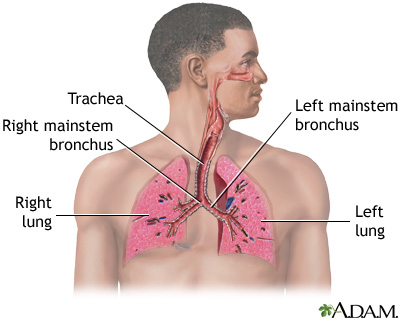

- Diffuse interstitial pulmonary fibrosis (deep lung tissues that become inflamed and then damaged)

- Spontaneous collapsed lung

- Lung problems that lead to lung failure

Avoid smoking. Quitting smoking can improve the outcome in people with Langerhans cell histiocytosis that affects the lungs.